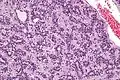

Low mag. High mag.

High mag.